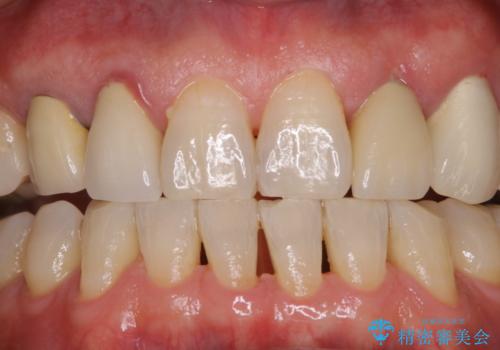

インビザラインでのマウスピース矯正中にクリーニングで口臭予防

- マウスピース矯正中に、口臭が気になりクリーニングを行いたいとのことでした。染め出しをしての歯ブラシ指導とPMTC60分コースを行いました。